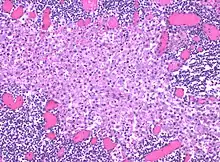

In medicine, histiocytosis is an excessive number of histiocytes[1] (tissue macrophages), and the term is also often used to refer to a group of rare diseases which share this sign as a characteristic. Occasionally and confusingly, the term "histiocytosis" is sometimes used to refer to individual diseases.